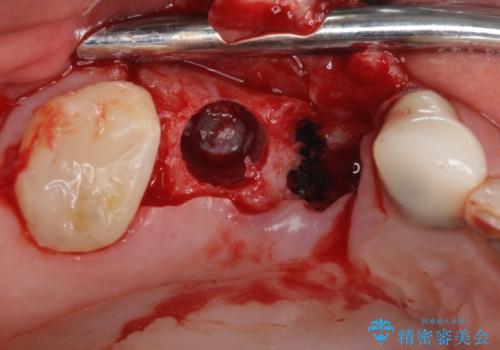

- 欠損や破折により失われた奥歯に、インプラント治療を希望して来院された患者様です。

欠損部はすぐにインプラント埋入が可能で、手前の歯根が残存している部位も、できれば抜歯をして奥と一緒に埋入をしたいところでしたが、破折による炎症が大きいため、2回に分けてインプラント埋入を行うこととしました。